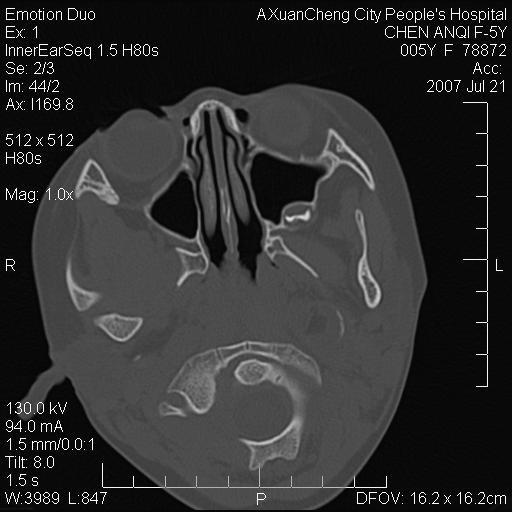

标题: PED0273:5岁,左耳流脓痛疼一周,颅底骨质破坏 [打印本页]

标题: PED0273:5岁,左耳流脓痛疼一周,颅底骨质破坏

患儿5岁,左耳流脓痛疼一周,左外耳道肉芽组织填塞 软组织窗显示病灶内结节状低密度影为气体密度

左侧中耳炎并胆脂瘤,左颞骨岩部骨质破坏并颅内感染积气。

考虑化脓性中耳乳突炎伴胆脂肪瘤形成并左颞叶感染,不除外合并嗜酸性肉芽肿.